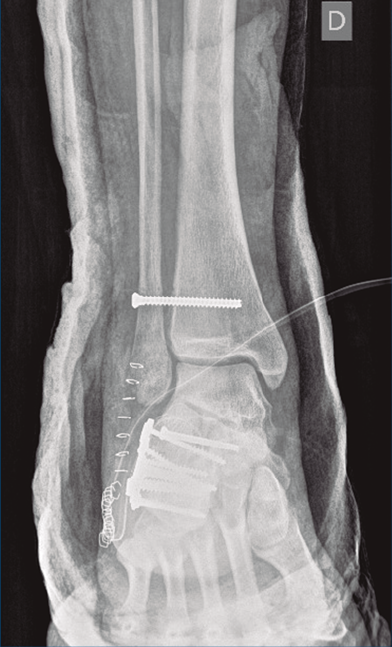

Bajo isquemia se realiza un abordaje lateral en L ampliado y se expone el calcáneo. Se trató de realizar una reducción abierta empleando un clavo de Steinmann (maniobra de Westhues), lo cual no se consiguió hasta la realización de un alargamiento percutáneo del Aquiles. Se comprobó bajo escopia la correcta reducción tanto de la fractura del calcáneo como de la luxación al nivel del tobillo. Se realizó una fijación con una placa de calcáneo, con 7 tornillos de esponjosa de 4 mm de diámetro (2 de ellos bloqueados) tras la reducción de la carilla posterior con un tornillo a compresión de 3,5 mm.

A continuación, pasamos a realizar un segundo abordaje lateral, respetando una separación suficiente para minimizar el riesgo de necrosis cutánea, a través de la cual se reparó la rotura del complejo ligamentoso lateral y se fijó la sindesmosis con un tornillo transindesmal de 4 mm de diámetro tras comprobarse bajo escopia la lesión al nivel de la articulación tibioperonea distal. Se inmovilizó mediante una férula posterior a 90°.

Figura 9. Control radiográfico posquirúrgico, anteroposterior.